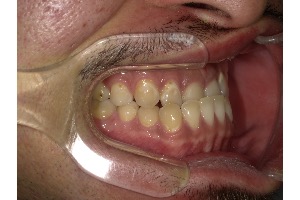

「受け口」とは、下の歯が上の歯よりも前に出ている噛み合わせのことを指し、専門的には「反対咬合」と呼ばれます。

受け口をそのままにしておくと、上下の歯の噛み合わせが自然な形からずれてしまい、食べ物をしっかり噛むことが難しくなります。その結果、以下のような問題が起こります

- 歯への偏った負担:噛む力が特定の歯に集中し、歯がすり減ったり、ひび割れたりする原因になります。